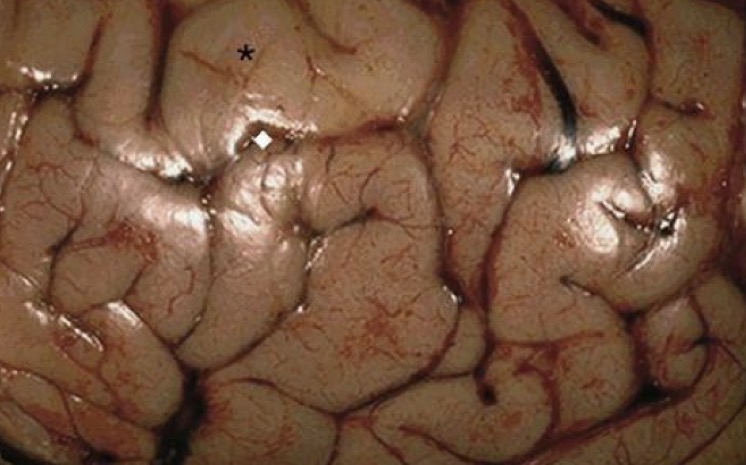

1. Identify the condition.

2. Describe the morphology?

3. What is the possible life-threatening complication in such a condition?

1. Cerebral edema.

2. The sulci are narrowed while the gyri are swollen and flattened.

3. Brainstem herniation.